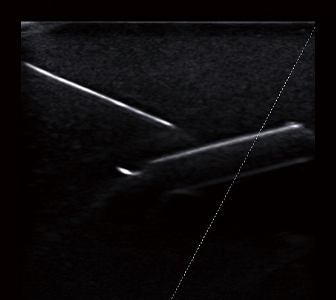

針先を見やすく。手技の精度と効率が向上。